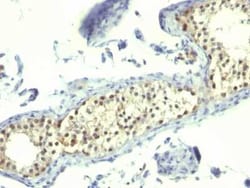

Thymidylate Synthase Antibody (TS106), Novus Biologicals™

Thymidylate Synthase Monoclonal specifically detects Thymidylate Synthase in Human samples. It is validated for Flow Cytometry, Immunohistochemistry, Immunocytochemistry/Immunofluorescence, Immunohistochemistry-Paraffin.

| It recognizes a protein of 36kDa, identified as Thymidylate Synthase (TS) (EC 2.1.1.45). TS converts deoxyuridine monophosphate (dUMP) to deoxythymidine monophosphate (dTMP), which is essential for DNA biosynthesis. TS is also a critical target for the fluoropyrimidines, an important group of antineoplastic drugs that are widely used in the treatment of solid tumors. Both 5-FU and fluorodeoxyuridine are converted in tumor cells to FdUMP which inactivates TS by formation of a ternary covalent complex in the presence of the folate cofactor 5,10-methylenetetrahydrofolate. Expression of TS protein is associated with response to 5-fluorouracil (5-FU) in human colorectal, gastric, head and neck, and breast carcinomas. | |